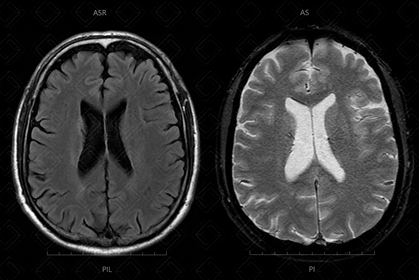

Texto alternativo para a imagem Figura 1. Créditos: Athena Hub/Medical Harbour

Descrição da figura 1: Na esquerda da imagem, observamos um sequência FLAIR (note que os ventrículos laterais estão pretos) e, à direita, sequência ponderada em T2.